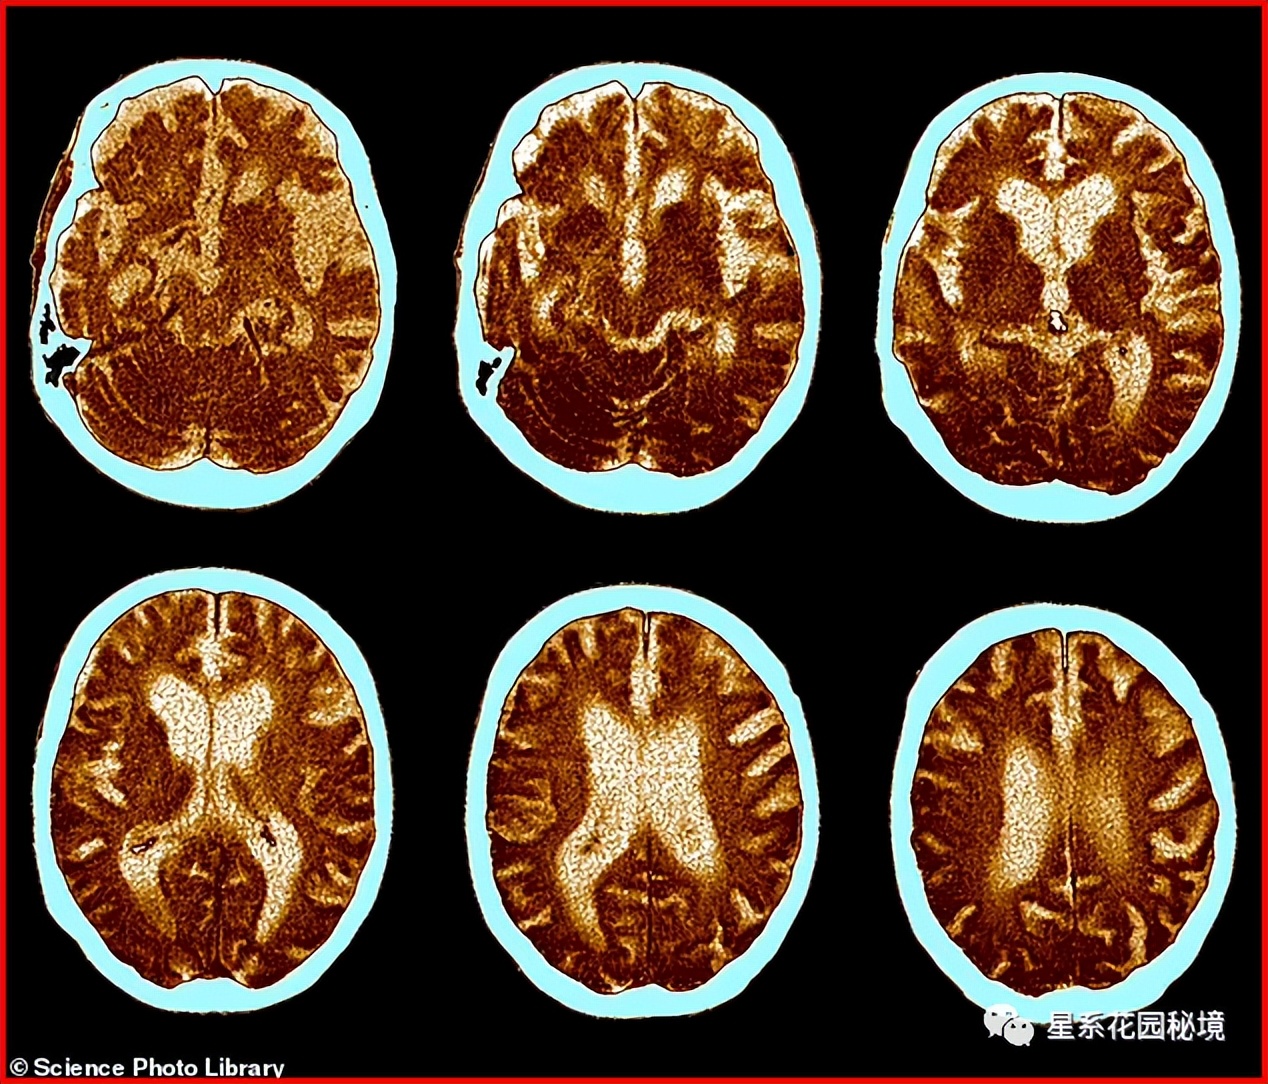

令人担忧的是,11月份公布的安全数据显示, 41% 服用该药物的患者出现了 严重的副作用 。其中最严重的包括一种称为 ARIA-E的大脑肿胀和出血 。FDA食药监局不良事件报告系统病例报告显示,至少有一名女性 死于 这种并发症。

霍华德教授说, 患者受到伤害,一些人直接死于服用一种甚至都不起作用的药物。如果,这都不算是学术造假,什么才叫造假?